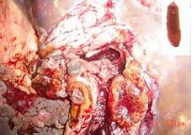

Trả lời:Bạn hãy bình tĩnh và hay xem lại các kết quả siêu âm cũng như các kết quả về xét nghiệm của bạn liên quan đến bệnh sán lá gan lớn như ELISA, bạch cầu eosin, …Chúng tôi nghĩ rằng, hiện nay với bệnh sán lá gan lớn thì thuốc điều trị đặc hiệu loại Triclabendazole vẫn còn rất hiệu quả, hình như với thông tin chủ quan của chúng tôi trên y văn và trong thực hành lâm sàng của chúng tôi điều trị trên 10.000 trường hợp thì chưa có trường hợp nào biểu hiện không đáp ứng cả, dù một số trường hợp chúng tôi phải điều trị đến liều thứ 2 hoặc thậm chí khoảng 0.5% điều trị đến liều 3 vì ổ dịch quá lớn và nặng. Chúng tôi rất tiếc không biết là trước khi điều trị bệnh sán lá gan lớn này thì kích thước tổn thương cũng như đặc điểm thương tổn gan của bạn như thế nào, cân nặng của bạn là bao nhiêu vì chúng tôi biết một số bệnh nhân dù cân nặng lớn hơn 50 kg, thậm chí trên 60kg mà các thầy thuốc vẫn điều trị chỉ có 2 viên tương đương 500mg thì không đủ liều cho điều trị cho bạn, điều này sẽ dãn đến thất bại điều trị do dùng dưới liều, bạn nên cho chúng tôi biết các thông tin cụ thể (có thể gọi cho chúng tôi theo số điện thoại BS Huỳnh Hồng Quang_0905.103496 để trả lời chi tiết hơn cho bạn).

Mặc khác, khi bạn bị sán lá gan thì triệu chức đau tức vùng gan là điều dễ hiểu, song sau khi điều trị bạn lại còn một số triệu chứng như bạn mô tả là có thể, nhưng rất hiếm bạn ạ. Thân chúc bạn khỏe và thông tin phản hồi lại cho chúng tôi biết sớm nhé.